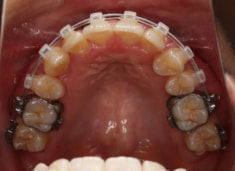

治療後(2年後)